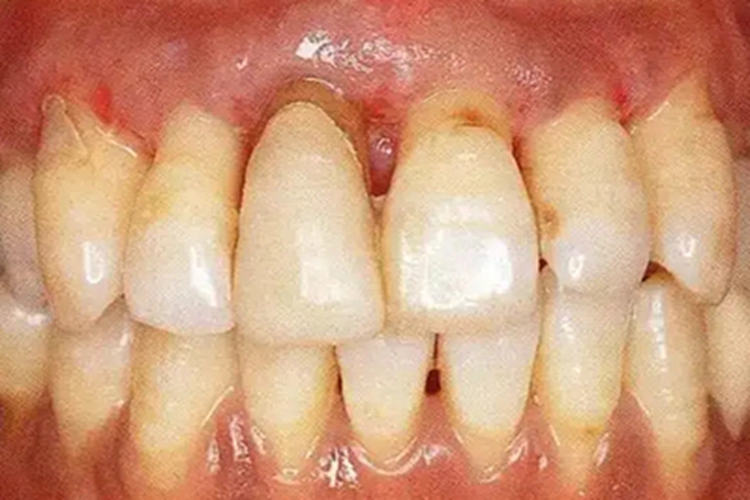

牙周炎早期不止有三大症状,一般表现为牙龈的慢性炎症,患者可有刷牙或进食时牙龈出血或口内有异味,但一般无明显不适。部分患者还可表现为少量黄色或褐色牙菌斑、牙石,以及深牙周袋的形成。

牙周炎早期出现上述症状时,建议患者及时在医生指导下实施洁治、刮治和根面平整等基础治疗,彻底清除感染,基础治疗后4-8周复查,必要时牙周手术治疗。可通过微生物学检查,明确龈下菌斑中的优势菌后,选用具有针对性的抗生素。